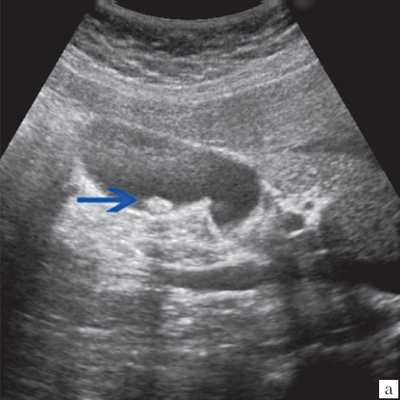

При использовании в 10 случаях допплеровских методов ни внутри полипа, ни в его ножке кровоток зарегистрировать не удалось (рис. 2). Дрожание полипов в виде пламени свечи, свидетельствующее об их тонкой ножке, вызывает движение расположенных рядом с полипом слоев желчи. В результате этого около полипа регистрируется цветовой сигнал.

![УЗИ. Холестериновый полип размером 22 мм, в режиме цветного допплеровского картирования кровоток не регистрируется]()

Рис. 2. Холестериновый полип размером 22 мм, в режиме цветного допплеровского картирования кровоток не регистрируется.

Ультрасонография является эффективным средством выявления полиповидной формы холестероза 9. Традиционной считается следующая сонографическая характеристика холестериновых полипов: неподвижные гиперэхогенные структуры, которые не дают акустической тени и прикрепляются к стенке желчного пузыря. Контуры таких образований, как правило, ровные, а размеры таких образований различны, чаще не превышают 10 мм (рис. 2).

![УЗ-картина полипов в желчном пузыре - режим ЦДК, кровоток не регистрируется]()

б) В режиме цветного допплеровского картирования кровоток не регистрируется.